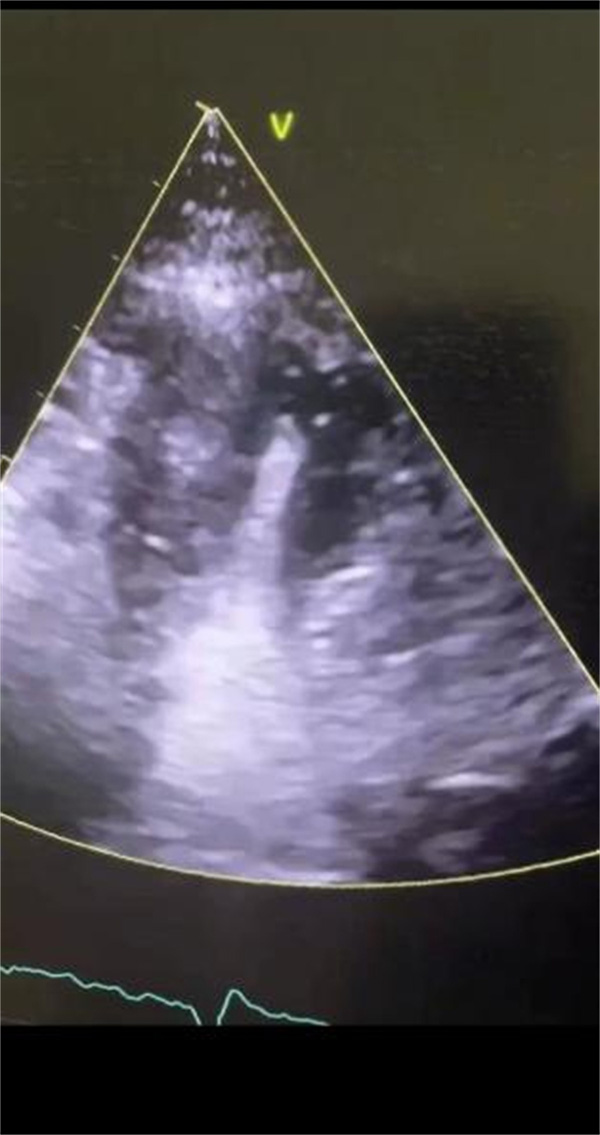

2022年也是超声心动全面发展的一年,2022年1月至今,心内科开展了心脏超声造影,包括左心腔超声造影、左心肌超声造影和右心超声造影,顺利完成了左心室血栓评估、心尖肥厚性心肌病、心肌致密化不全、PCI手术患者术前、术后心肌灌注评估、透析患者心肌的评估。

心脏超声造影通过外周静脉注射超声造影剂(ultrasound contrast agent,UCA),实时动态且更清晰地观察心肌灌注及心腔,反映心脏结构、功能及其冠脉微循环。

定量评价左室容量、射血分数、节段性运动异常(与核素显象、磁共振有良好的相关性),观测心脏内部细微解剖结构(左室心尖肥厚、心肌致密化不全、心尖血栓、心尖室壁瘤),能更清晰的显示左心房的解剖特征,尤其是左心耳,对鉴别血栓、伪像、明显自发显影和左心耳正常解剖结构有很大帮助。